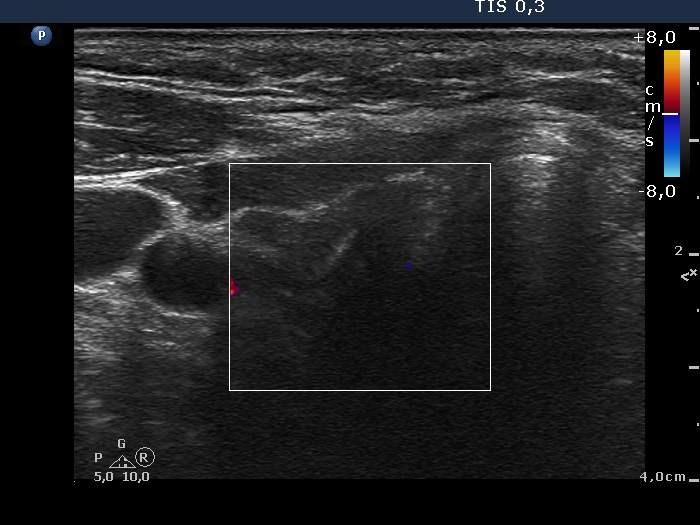

Discrete lesion or nodule in Hashimoto's thyroiditis - case 15 (714) (ultrasonographic picture 6)

Lowest part of the right lobe, transverse view, color Doppler mode. The lesion is avascular.